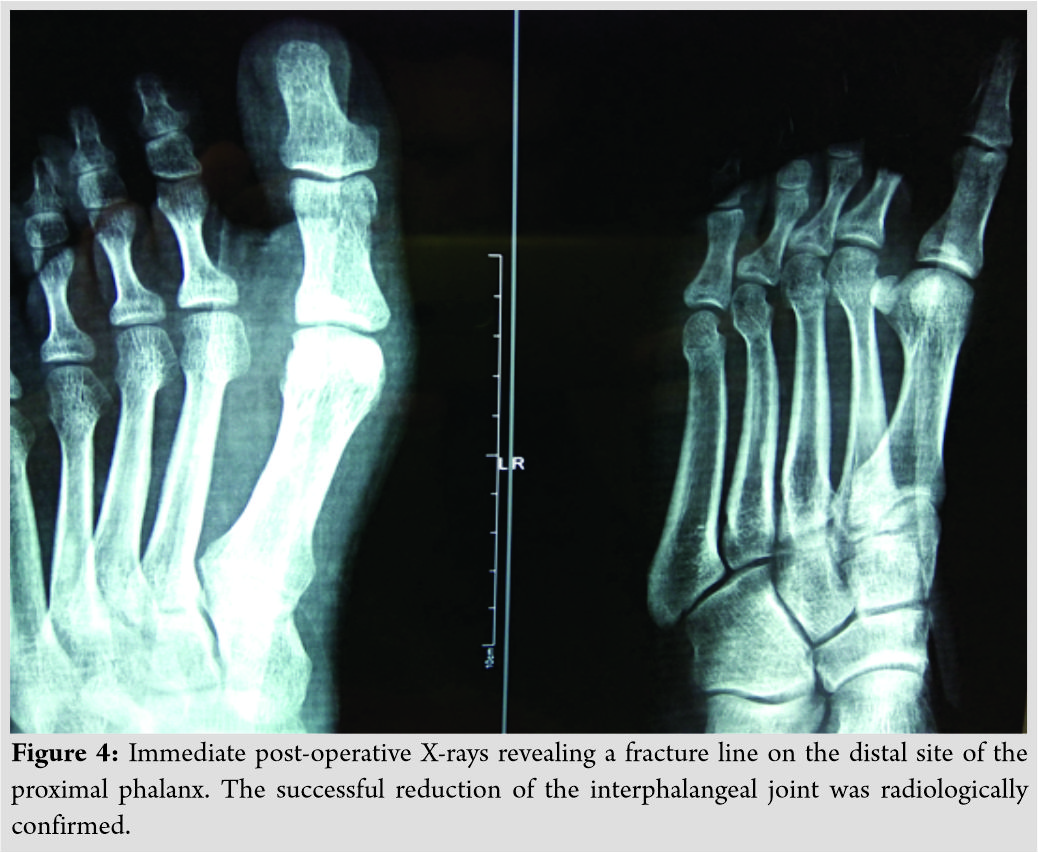

The IP joint was evaluated after the closure and was found to be stable. Immediate post-operative X-rays confirmed the successful reduction of the joint, but they also revealed a non-displaced, minor linear fracture of the proximal phalanx (Fig. 4). To avoid post-operative infection, antibiotics (ciprofloxacin and clindamycin) were provided intravenously for the first 3 days and then per os for 5 more days.